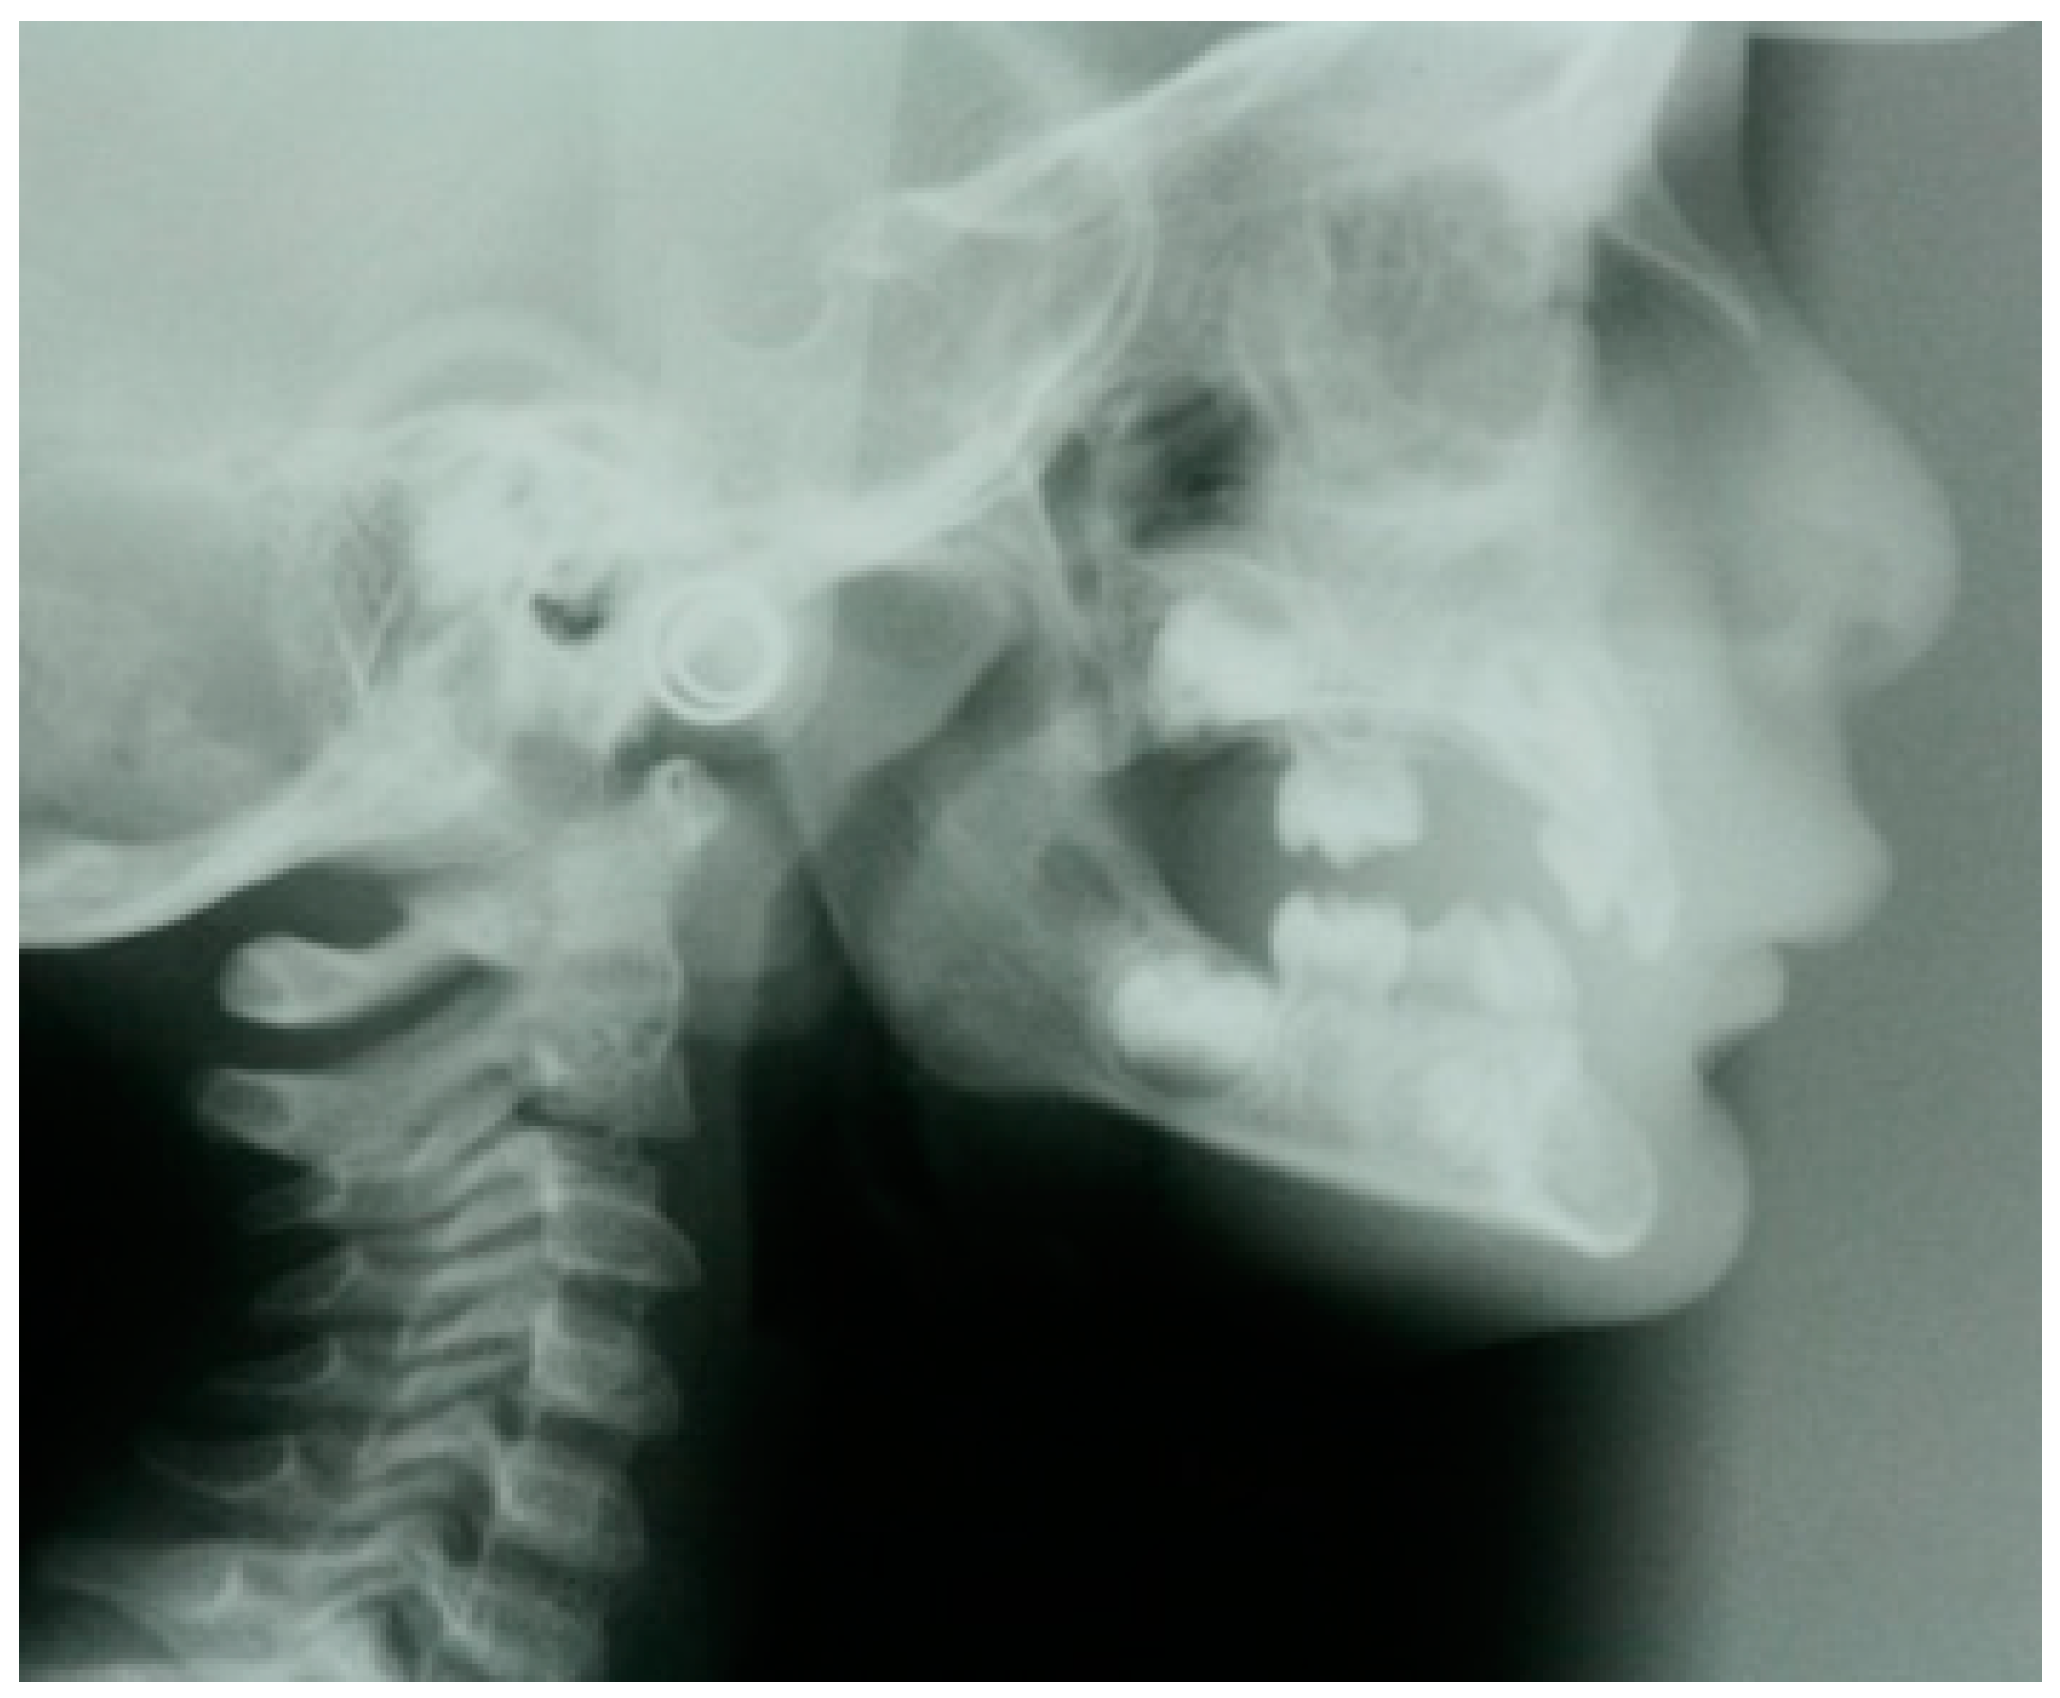

- Sasaki, Y.; Kaida, C.; Saitoh, I.; Fujiwara, T.; Nonaka, K. Craniofacial growth and functional change in oligodontia with ectodermal dysplasia: A case report. J. Oral Rehabil. 2007, 34, 228–235. [Google Scholar] [CrossRef]

- Celli, D.; Manente, A.; Grippaudo, C.; Cordaro, M. Interceptive treatment in ectodermal dysplasia using an innovative orthodontic/prosthetic modular appliance. A case report with 10-year follow-up. Eur. J. Paediatr. Dent. 2018, 19, 307–312. [Google Scholar] [CrossRef] [PubMed]

- Cerezo-Cayuelas, M.; Pérez-Silva, A.; Serna-Muñoz, C.; Vicente, A.; Martínez-Beneyto, Y.; Cabello-Malagón, I.; Ortiz-Ruiz, A.J. Orthodontic and dentofacial orthopedic treatments in patients with ectodermal dysplasia: A systematic review. Orphanet J. Rare Dis. 2022, 17, 376. [Google Scholar] [CrossRef] [PubMed]